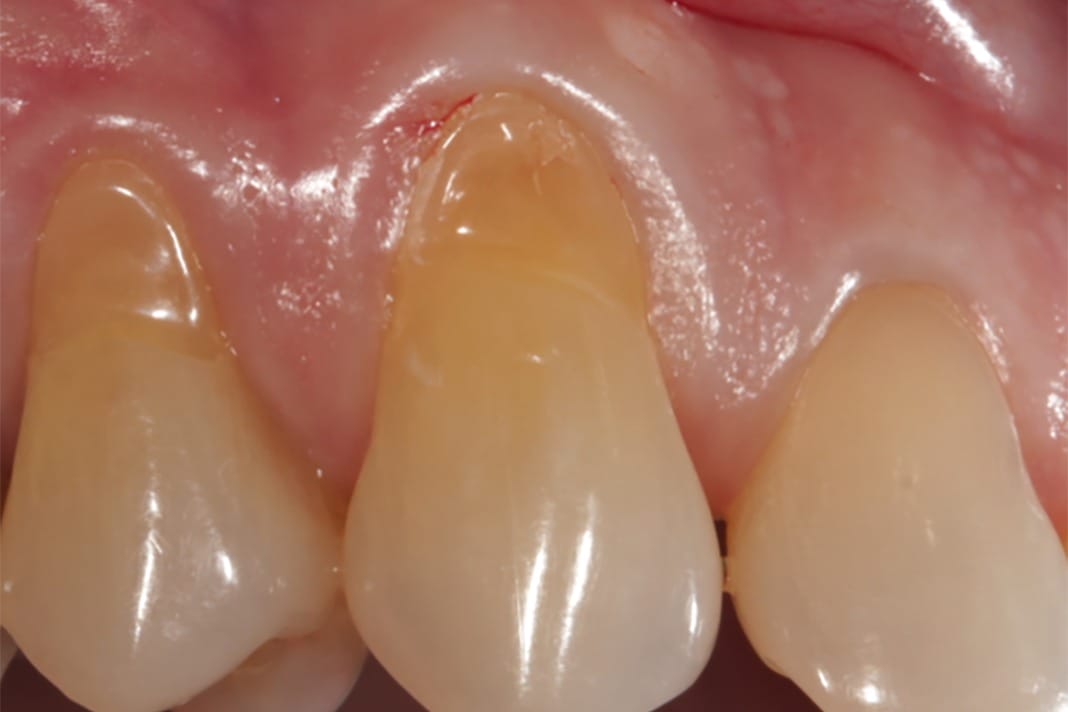

Gingival recession is something most of us see in our patients’ on a daily basis. It is defined as the apical migration of gingiva, which can cause various problems for our patients, including sensitivity, periodontal complications, esthetic concerns, and decay.1 Gingival recession results from many different factors, such as patient habits (i.e., picking with their fingernails), periodontal disease, bruxism, and orthodontic treatment.

The second type of autograft is the free gingival graft; this graft is similar to the first but differs in the fact that the tissue taken from the donor site of the patient includes the top portion of keratinized tissue as well as the underlying layer of epithelium. This type of graft can be used in areas similar to the subepithelial connective tissue graft but may not be the best option for areas that are of aesthetic concern because the tissue taken can be thicker and bulkier in appearance and not match the surrounding tissue color.1,3